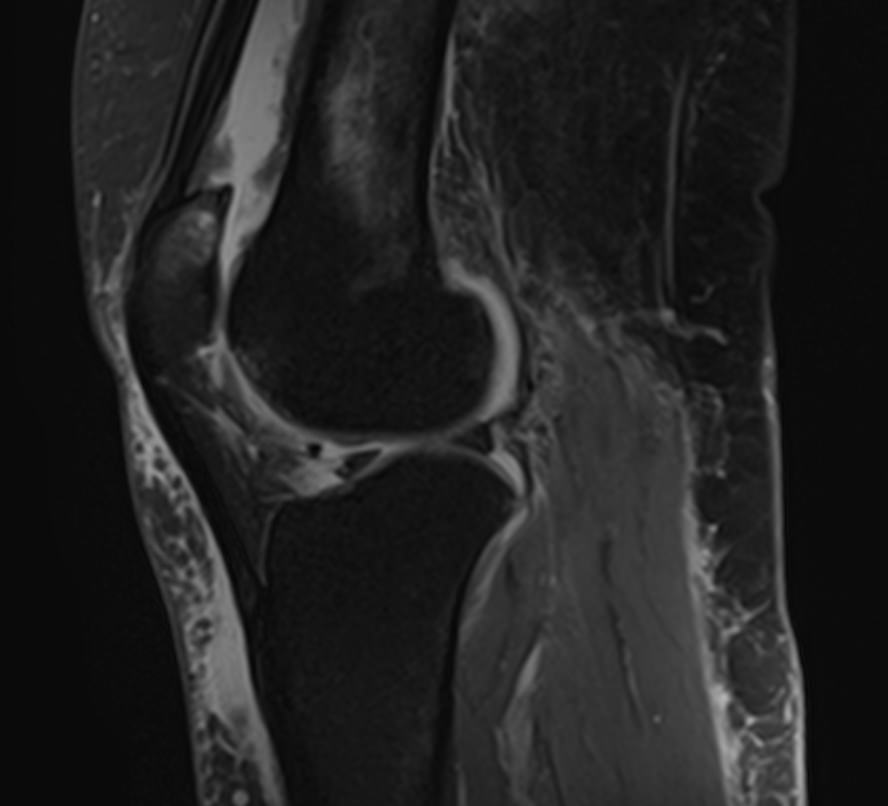

Пояснично-крестцовый отдел позвоночника выполняет основную опорную функцию, поддерживая устойчивость тела. Нижние отделы позвоночника и крупные суставы нижних конечностей, в частности, коленные суставы, испытывают интенсивные нагрузки, поэтому часто подвержены развитию воспалительных и дегенеративно-дистрофических заболеваний.

При сочетанном поражении этих анатомических областей целесообразно проведение комплексной МРТ, включающей обследование пояснично-крестцового отдела позвоночника и коленных суставов.

Томограф позволяет детально визуализировать состояние всех анатомических структур позвоночного столба на исследуемом уровне, костные структуры колена и окружающие мягкие ткани данных анатомических областей, включая мышцы, связки, нервные сплетение, сосуды.

• дегенеративно-дистрофическое поражение коленных суставов (гонартроз);

• воспалительные заболевания коленных суставов (артриты, синовиты);

• врожденные пороки развития коленных суставов (дисплазия, аплазия);

• доброкачественные и злокачественные опухоли коленных суставов и окружающих их тканей.